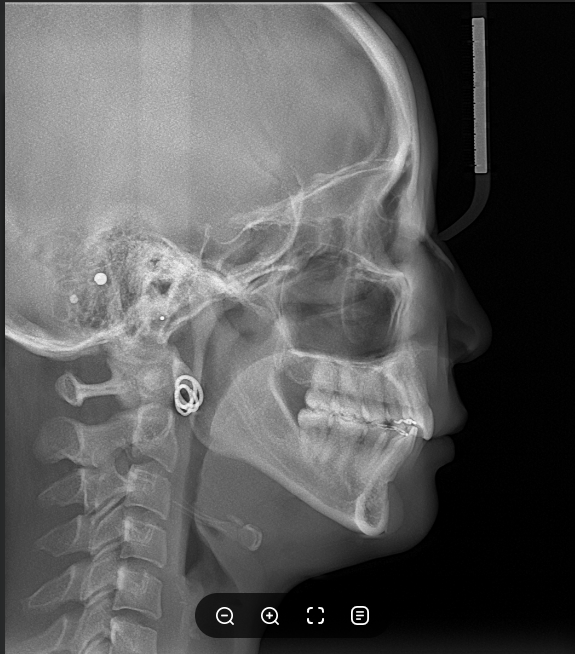

그래서 환자분의 경우 상악 치아에 미니스크류를 식립하고 상악 치열 전체를 후방으로 이동시켜드렸습니다. 발치를 하지 않고도 충분히 개선해볼 수 있었죠. 비발치로도 충분히 돌출입 교정을 진행해본 건데요. 여기에 심한 무턱 증상의 경우 환자분의 구강상태에 따라 다를 수 있는데 발치유무의 경우 환자마다 허용치가 다르기 때문에 상세한 설명 후 논의를 거쳐 진행해볼 필요가 있었어요. 환자분의 경우 상악에 먼저 미니스크류를 식립해 진행했고 이후 상하악 소구치 발치 공간을 이용해 상악 전치를 뒤로 넣게 플랜을 수립했습니다.

이후 사진을 보면 앞니의 뻐드러짐이 사라진 것을 확인할 수 있었는데요. 돌출입 증상과 무턱 증상 모두 개선해 안모 변화가 크게 변화된 것을 확인할 수 있었습니다.

파노라마 사진을 보면 더 확연히 확인할 수 있죠. 앞니의 뻐드러짐과 돌출입, 무턱을 모두 개선할 수 있는 치아교정. 수술없이도 안모 변화가 크게 개선된 것을 보면 정말이지 뿌듯합니다. 환자분의 경우 치료 종료 후 8년이 지난 파노라마 사진으로도 교정 후 잘 유지되고 있다는 것을 확인할 수 있었는데요.